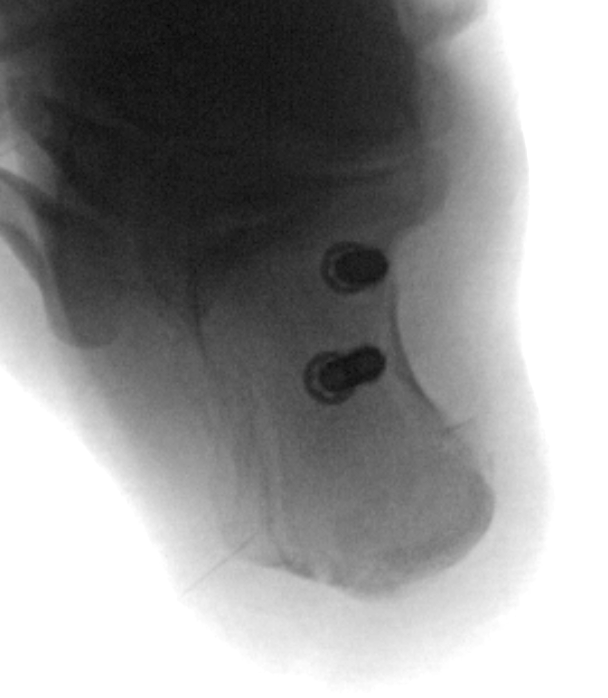

ORIF

Reduce fracture with clamps

Insert 2 - 3 screws

- bicortical fixation

- anterior to weight bearing posterior tuberosity

- cast with foot plantar flexed